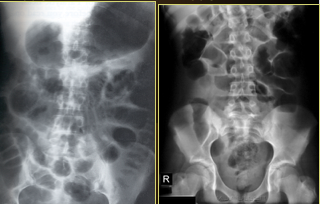

Which one is small v. latge bowel obstruction?

top: small bowel w/valvulae conniventes

bottom: large bowel w/haustrations